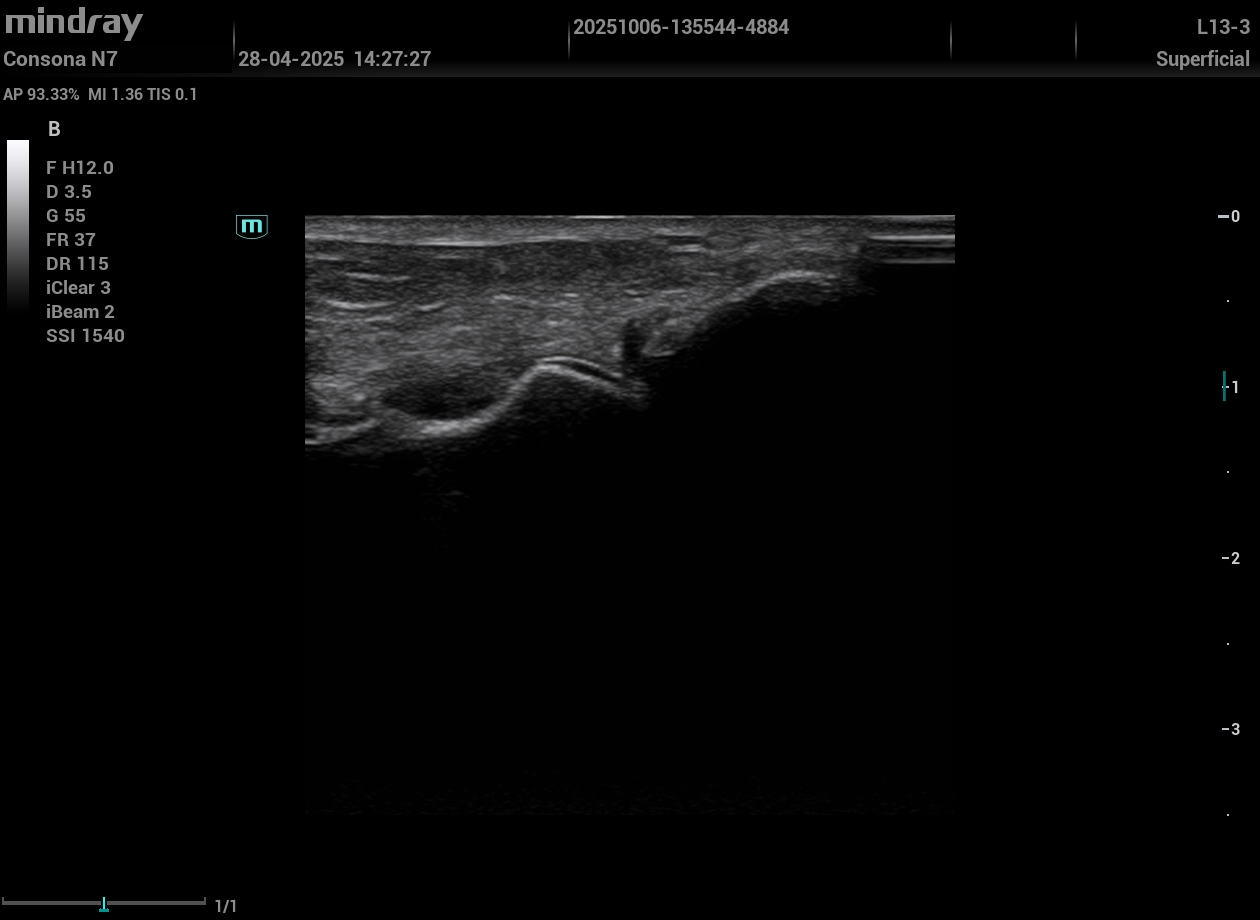

Dolor postquirúrgico en pared abdominal: la paciente, recién intervenida de histerectomía, temía una complicación. La ecografía mostró un hematoma superficial sin complicaciones. Evitamos traslado y ganamos confianza.